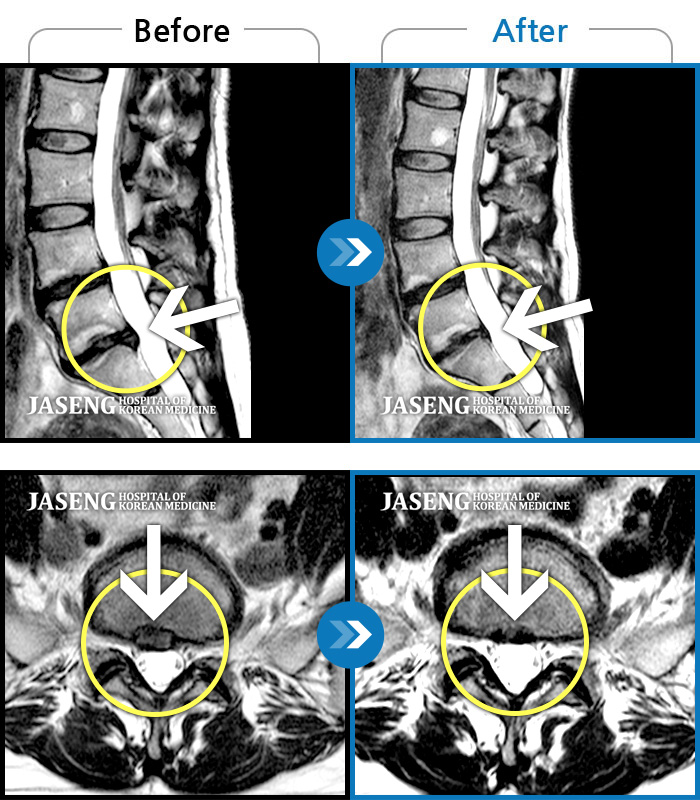

자생 비수술 한방통합치료 후

터진디스크가 흡수된 모습

Before

터진디스크 한방통합치료 전

After

터진디스크 한방통합치료 후

비수술 치료만으로

터진 디스크 흡수

튀어나온 디스크 대비,

터진 디스크 치료 효과 우수

디스크 흘러내린 정도가

심할수록 흡수 가능성 증가

치료 후 장기추적관찰 결과,

환자 90% 이상 치료 만족